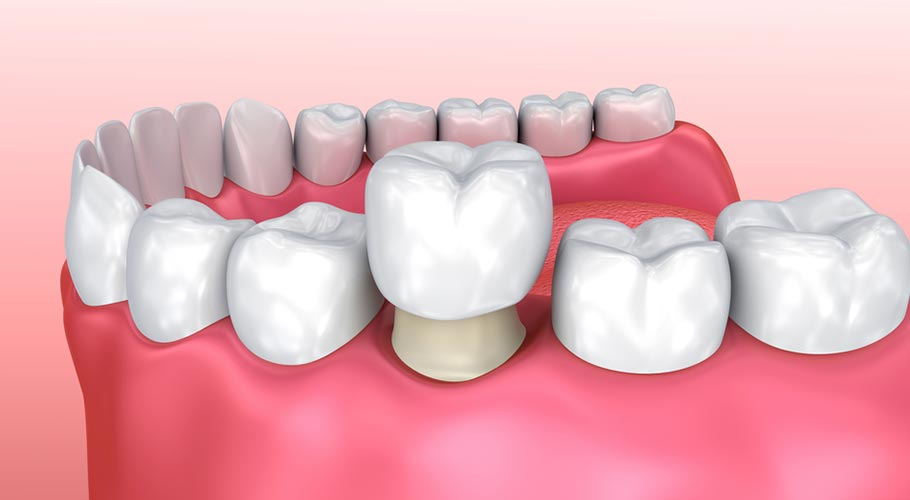

Bọc răng sứ

Bọc răng sứ ngày càng được nhiều người ưa chuộng vì đem lại vẻ thẩm mỹ tối ưu cho tất cả trường hợp mẻ răng cửa. Các răng trước khi được bọc sứ sẽ cần phải được mài chỉnh để cho ra tỷ lệ nhất định để khi chụp sứ lên phần răng không bị cộm.

Thời gian bọc răng sứ cho răng cửa bị mẻ thường là 2 – 4 ngày. Sau khi thực hiện, khách hàng đạt được kết quả như mong muốn. Những ưu điểm khi lựa chọn bọc răng sứ cho răng cửa bị mẻ là: